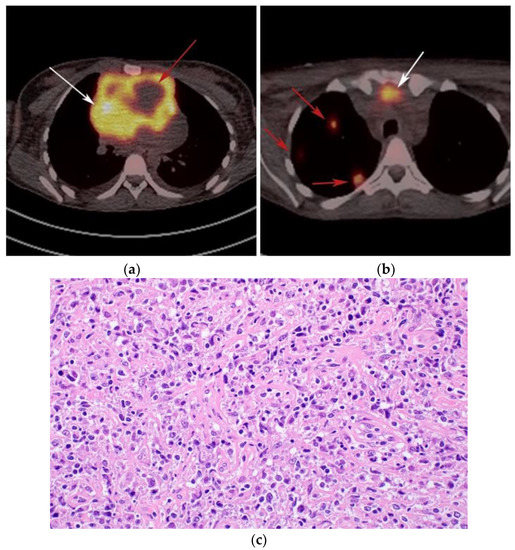

Figure 6.

Imaging in a different patient with known diagnosis of primary mediastinal B-cell lymphoma. (a) Axial FDG PET/CT images show the hypermetabolic anterior mediastinal mass (white arrows), and there is also central areas of absent metabolic activity within the mass (red arrow), correlating with areas of fibrosis, a finding that is essential in prebiopsy planning to avoid false negative results. (b) Axial FDG PET/CT images show hypermetabolic right upper paratracheal nodes (white arrows) and several additional hypermetabolic pulmonary and pleural-based nodules within right upper lung (red arrows). (c) H&E section shows that the tumor is composed of large, atypical cells with reniform or multi-lobulated nuclei with abundant clear cytoplasm. Note the lymphoma cells are compartmentalized by the prominent sclerotic bands of fibrosis. (Original magnification 400x, H&E stain).